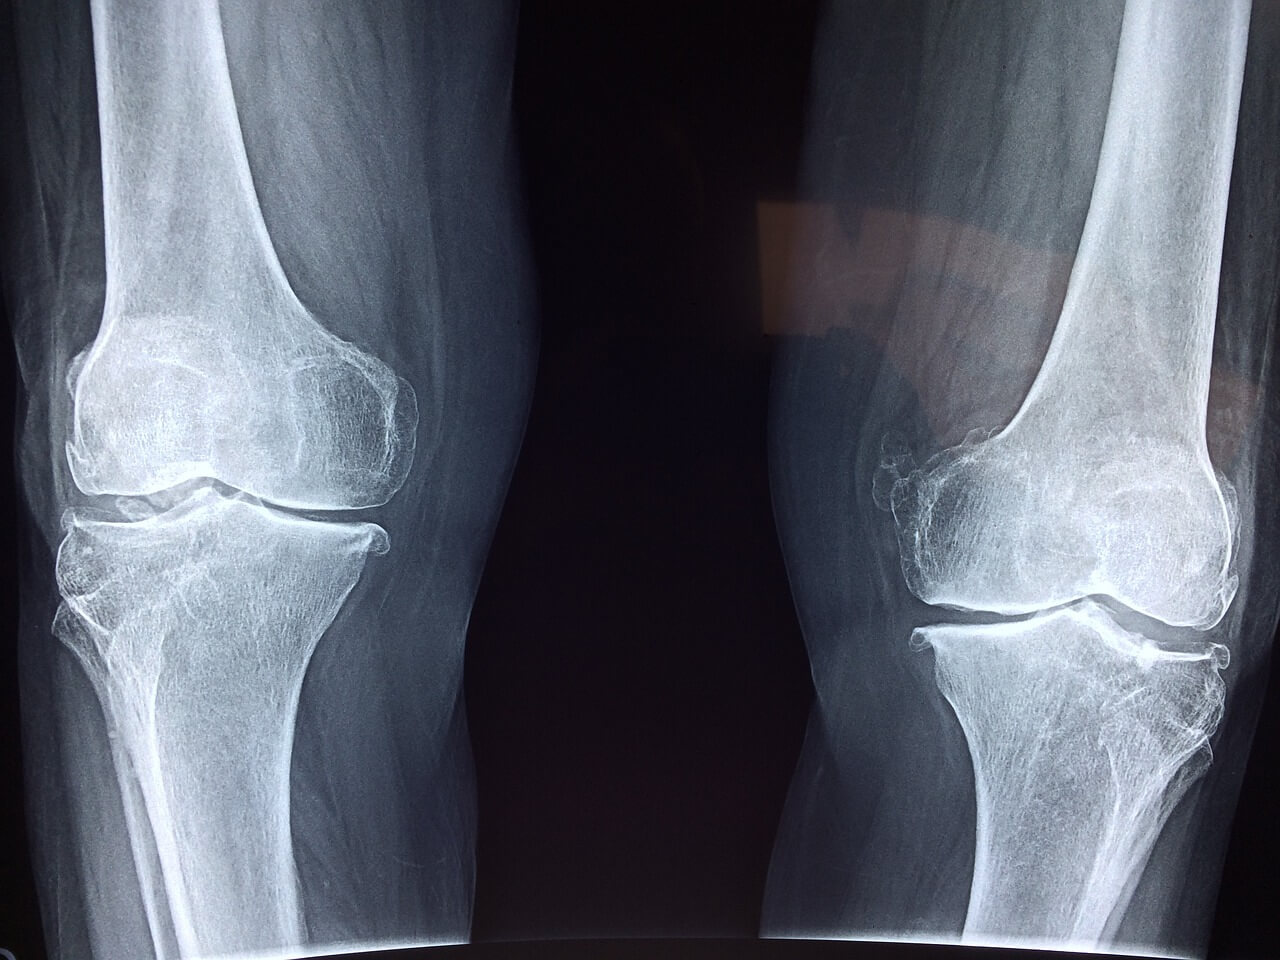

3) 척추 휘어짐, 오다리 증상

꼬부랑 할머니 이야기는 많이 들어보았으나 꼬부랑 할아버지 이야기는 거의 들어본 적 없지요? 여성은 남성에 비해 나이 들수록 뼈가 약해지기 때문에 척추나 다리가 휘어지는 경우가 더 많습니다. 외관상 보기 좋지 않음은 물론이고 건강상에도 좋을 리가 없습니다.